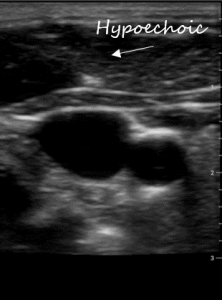

Communication works best when were are all using the same language. Describing ultrasound images is no different. All ultrasound terms are based on describing how sound is reflected. Below are terms used to describe the appearance of body structures on ultrasound:

Gain: this can be thought of as the ‘brightness’. The higher the gain the whiter things get; the lower the gain the darker things get. Gain is a processing function and doesn’t change any of the characteristics of the ultrasound beam itself. Optimal gain is achieved when anechoic structures like fluid or blood are black and hypoechoic tissue like subcutaneous tissue or organs are grey and hyperechoic structures like arterial walls, pleura, and bone are white.